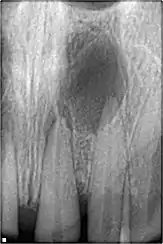

Résection apicale

Les objectifs de la résection apicale sont :

- retirer une partie de la racine qui ne pourrait être désinfectée ou/et remplie avec un matériau de remplissage de canal et dont les contenus peuvent avoir causé ou maintenu une inflammation,

faciliter l'accès pour la création d'une préparation de terminaison radiculaire, en vue d'un remplissage de terminaison radiculaire. L'apex doit être réséqué avec peu ou pas de biseau. Le procédé lui-même est rarement utilisé, et seulement quand on a considéré que le canal radiculaire a été traité de façon satisfaisante, et bien rempli.

- Préparation et remplissage de terminaison radiculaire

La préparation de la terminaison radiculaire est pratiquée après la résection de l'apex. Cela doit suivre les contours du système canalaire et être dans l'axe du (des) canal(aux). L'objectif du remplissage de terminaison canalaire est de remplir cette cavité et de fermer toute communication du canal radiculaire aux tissus péri radiculaires. Un matériau de remplissage est placé dans la cavité de la terminaison radiculaire. L'amalgame n'est plus le matériau de choix.